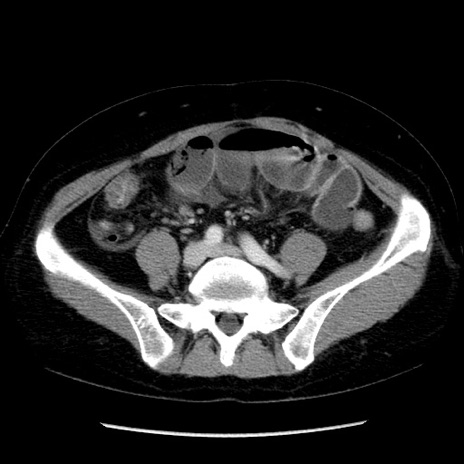

矢状断像